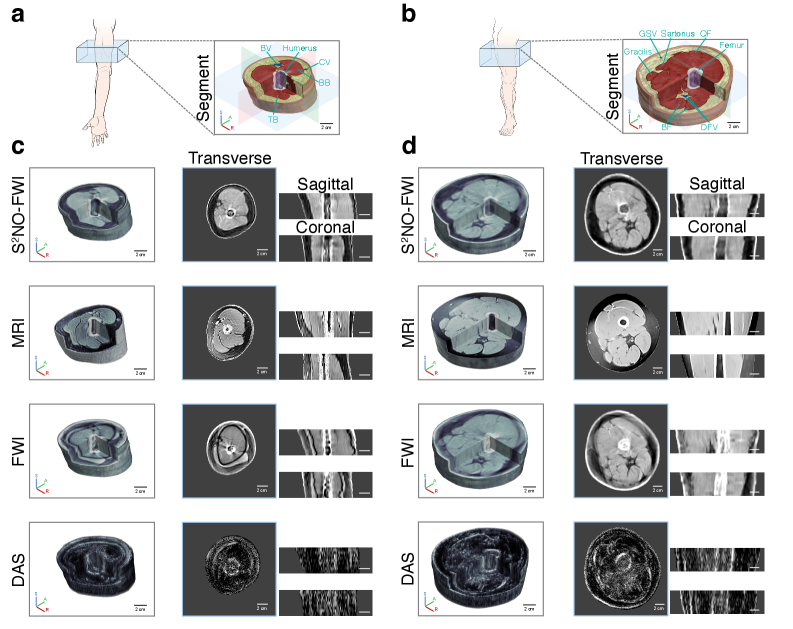

Figure 6a,d and Fig . 7a,c present 3D reconstructions of the arms from both female and male subjects obtained via various methods. The segmented and color‐coded reconstructions demonstrate that the S2NOS^{2}NO‐based inversion effectively restored arm anatomy by the distinct delineation of the skin, humerus, blood vessels (e.g., brachial and cephalic veins), and muscles (e.g., biceps brachii and triceps brachii), while also providing quantitative acoustic maps that reflect muscle stiffness and bone integrity. Moreover, distinct muscle–bone interfaces not only facilitate differentiation between male and female arms based on muscle ratios but also enable the extraction of muscle metrics such as cross-sectional area and volume, which may assist in the diagnosis of sarcopenia (?, ?). Reference MRI images from the same subjects are provided as a gold-standard comparison. Notably, S2NOS^{2}NO outperformed other methods, delivering high-resolution reconstructions with a parameter-free resolution of 1.09 mm, closely approaching the MRI standard of 0.88 mm. Sagittal and coronal cross-sectional reconstructions further demonstrate the consistent performance of S2NOS^{2}NO across different imaging planes. In contrast, the numerical solver, CBS, exhibited scattering artifacts near bone structures and distinct black-ring artifacts in arm reconstructions, indicating that traditional numerical solvers are less robust in strongly scattering samples and tend to overfit to observational noise. In comparison, the S2NOS^{2}NO-based approach demonstrated superior stability.

In Vivo 3D Human Legs

Finally, we applied our method to high-resolution 3D UT imaging of human legs—a challenging yet crucial task for diagnosing sports injuries (e.g., muscle strain, Achilles tendon rupture) and musculoskeletal conditions (e.g., age-related osteoporosis). Using S2NOS^{2}NO-FWI, we achieved high-fidelity 3D reconstructions closely matching reference MRI results (Fig. 6b,d and Fig. 7b,d). For two healthy volunteers (IRB Approval No. IRB00006761-M2024690), we reconstructed 11 mid-thigh slices spanning approximately 5 cm and combined them to yield a 3D sound speed model. Semantic segmentation of the reconstructed volumes (Fig. 6b and Fig. 7b) indicates that S2NOS^{2}NO accurately delineates skin, muscle (e.g., biceps femoris, gracilis, sartorius), fat, blood vessels (e.g., deep femoral vein, great saphenous vein), and femoral structures—including low-density marrow—with a parameter-free resolution of approximately 1.30 mm, an achievement unattainable using classical DAS. The strong scattering in musculoskeletal tissues results in observed signals with extremely low signal-to-noise ratios, complicating the accurate determination of first-arrival times and ultimately causing ToFT to fail in arm and leg imaging applications. Compared to traditional FWI, which required over 133 minutes (around 2.2 hours) for reconstruction per slice, S2NOS^{2}NO completed the imaging under 10 minutes using one NVIDIA A800-80GB GPU. Notably, S2NOS^{2}NO-FWI’s speedup over conventional FWI grows from about 6× for arm imaging to 14× for leg imaging, revealing its superior performance on stronger scattering PDEs. This enables the first successful 3D UT-FWI imaging of human legs, delivering quantitative biomechanical maps that support the diagnosis of conditions rooted in tissue mechanics, such as osteoporosis or muscle degeneration, and underscoring the method’s strong potential for efficient clinical applications where timely diagnosis is critical.

Figure 7: The 3D UT imaging of a male’s leg and arm. (a-b) The color-coded segmentations of S2NOS^{2}NO-based FWI reconstruction results are shown for 3D arm (a) and leg (b). (c) 3D reconstructions of the male arm, obtained by S2NOS^{2}NO-based FWI, MRI, traditional FWI and DAS, were assembled from 11 segmented slices. Representative transverse, sagittal and coronal sections obtained by different imaging methods are also provided. (d) 3D reconstructions of the male leg, obtained by S2NOS^{2}NO-based FWI, MRI, traditional FWI and DAS, were assembled from 11 segmented slices. BF, biceps femoris; QF, quadriceps femoris; DFV, deep femoral vein; GSV, great saphenous vein; BB, biceps brachii; TB, triceps brachii; BV, brachial vein; CV, cephalic vein.